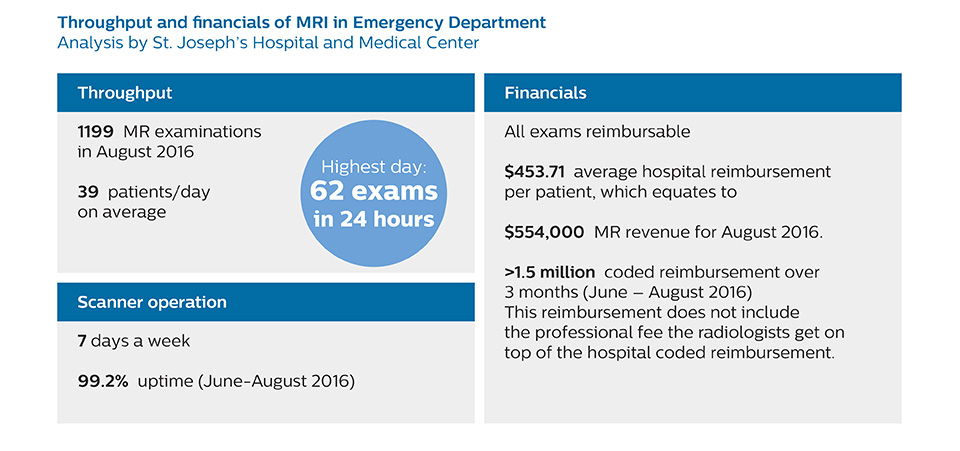

In order to address efficiency, matched with state-of-the-art capabilities to support a rich diagnosis, the decision was taken to include a Philips Ingenia 1.5T MRI scanner with wide bore in the new setup of the ED to enable scanning of virtually all patients.

To minimize the time taken to perform scans, rapid MRI examination protocols (ExamCards) were developed, shortening the total scanning time to even less than 10 minutes in some exams. Techniques like mDIXON (modified DIXON) are used for robust capturing of fat-free MRI images in a hectic ED environment.

A range of protocol sheets was developed to help ensure that referring physicians order the most appropriate MRI exam. The optimized MRI protocols also include 3D contrast-enhanced imaging, allowing neurosurgeons to comfortably use the isotropic data in the operating room while performing stereotaxic surgery.

After the MRI scanning, the preliminary reports are made available to referring physicians more quickly than before, because that is what physicians need to make their decision on what to do with patient. Using a redesigned reporting process results in total turnaround times that are similar to those of CT. Another of the changes introduced is that MRI safety screening data are retrieved from the hospital information system, saving approximately 30 minutes.

The transition away from a predominantly CT-based ED began by educating physicians about the advantages of MRI in the emergency setting, when to use MRI, and the importance of targeted exams instead of broader, non-targeted exams. Some resistance to the change was anticipated, as it was disrupting established routines, so a reasonable amount of time was planned for educating referrers, neuroradiologists and neurosurgeons, as well as residents and fellows. However, less time than anticipated was needed: all involved were already familiar with MRI and, more importantly, they were easily persuaded on learning about the 10-minute exam duration with MRI.

“We bring forward that the MRI exam time is similar to CT, which is very important to them”, says Dr. Karis. “One of the other points to stress is that the MRI scanner is available for targeted exams only. This requires referrers to think clearly about what they want to test. There must be a true commitment to the shorter time frame; otherwise, the process won’t work.”

The ED physicians can only request exams from a selected set of available exam protocols – as represented on the protocol sheet – minimizing the time necessary for the MRI scan. The sheet contains advice as to which scan to order (i.e. MRI vs. CT, contrast vs. non-contrast) depending on the situation, and encouraging physicians to order targeted scans. Even though the process has now been implemented, education still remains important; new neurology residents, for example, are informed as to the use of the ED MRI scanner, how it’s being utilized, and the importance of targeted scanning. “In my opinion, education has been crucial to establish the MRI exam as an ED test,” says Dr. Karis. “This is really key. If you can’t establish this concept, then you can’t convert everyone to the mindset that this is an ED test.”

Patient turnaround times on par with CT

“Before, when patients received CT in the ED, it was quite common that they would need an MRI afterwards. However, in the four months that I have logged data for this study, I have not become aware of a single patient that underwent MRI in the ED and had to come back for repeat imaging, probably because the protocols are so robust. Patients with complicated cases requiring specialty acquisition types are the most common reason for recalls at our institution.”

“Our results show that a dedicated MRI in the ED can be effectively implemented; patient turnaround times with MRI were on par with CT. Interestingly, even though the MRI exam protocols were shortened, this robust yet rapid scanning still yielded good quality images, further improving our workflow and almost eliminating the need for repeat scans or follow-up scans. So, we’re heading towards first time right imaging,” says Dr. Karis.

At St. Joseph’s Hospital and Medical Center, the dedicated MRI system in the ED has been shown to efficiently provide high quality MR images that assist physicians in making informed decisions on patient diagnoses and take a more definitive decision on follow-up. The decision to have a dedicated ED MRI has resulted in rapid patient turnaround, efficient patient management, and substantial reductions in radiation dose.